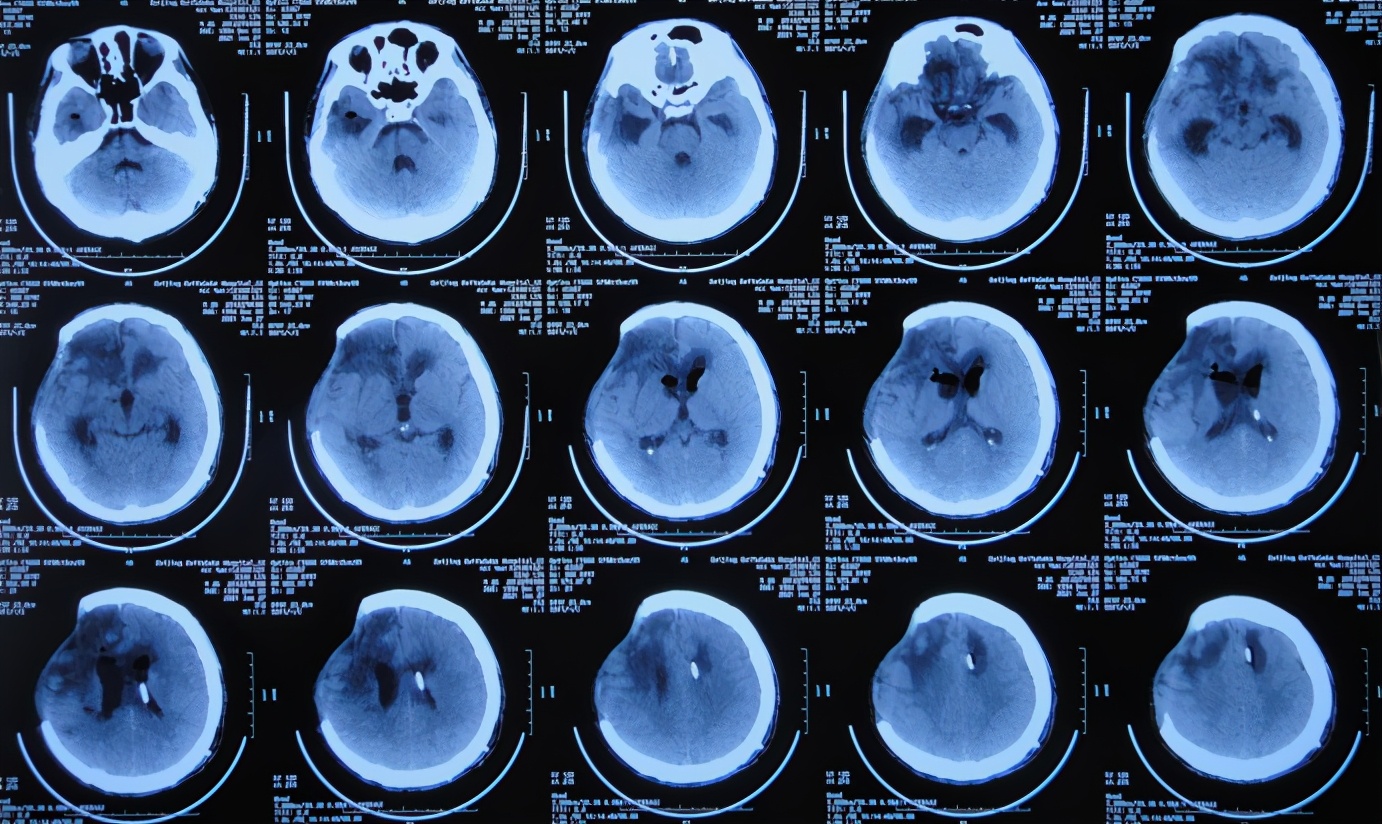

开颅术后15天即2020年12月27日(脑室外引流术后2天)住入李小勇脑脊液科。入院时:昏迷,刺痛后双上肢无反应,鼻饲饮食,大小便不能自理,体温升高38.2°C,携带外院引流管,气管插管( 图-9 );头颅CT示脑积水,脑膨出( 图-10 )。

图-10: 2020年12月27日头颅CT

入院治疗第2天即2020年12月28日,进行了右侧的脑室外引流术,头颅CT示脑室内有2根管( 图-11 )。

图-11: 2020年12月28日头颅CT

入院治疗5天即2021年1月1日,查头颅CT示脑积水和脑膨出均有减轻( 图-12 )。

图-12: 2021年1月1日头颅CT